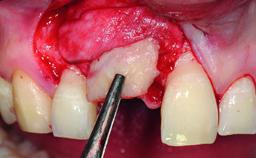

Replacement of a Missing Upper Left Central Incisor: Late Placement of an RC Bone Level Implant, CAD/CAM Zirconia Abutment

A healthy 37-year-old female patient was referred for a consultation on the replacement of missing tooth 21 with an implant-supported restoration. She stated that several years previously the tooth had been traumatically avulsed following a motor vehicle accident. The tooth was replaced with a three-unit fixed partial denture (FPD) immediately afterwards. Over time, she became disillusioned with the FPD and looked for a different option, including orthodontic therapy. She presented still in her orthodontic appliances, with the pontic sectioned free from the FPD but attached to the archwire. Her orthodontist felt that orthodontic treatment had been successfully completed, but nevertheless referred her before removing the appliances in case adjustments were necessary.

| Bone Augmentation | Horizontal|Simultaneous |

| Augmentation Materials | Xenogenous|Membrane |

| Soft Tissue Grafting | Simultaneous |